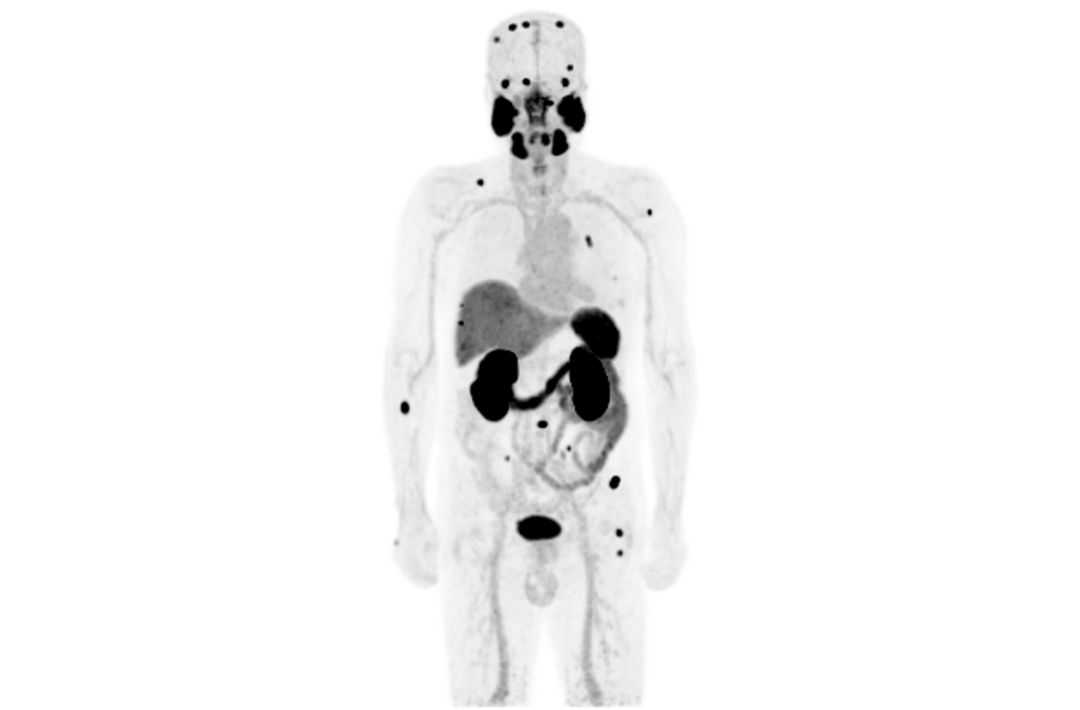

However, since the launch of integrated PET/MR more than ten years ago, there have been limitations on scan efficiency. The short AFOV of PET fails to meet the needs of whole-body imaging, so it’s been necessary to scan patients over multiple bed positions, which increases the scan time and reduces patient throughput.

Compared with the conventional PET system with AFOV ranging between 20cm and 25cm, the 32cm long AFOV not only improves the sensitivity of the system, but also basically covers main organs of the whole body and the regional lymphatic system where metastasis may occur, and makes it possible to realize cancer TN staging in one bed position.

Traditionally, a PET/MR scan of a tumor patient takes about 35 to 50 minutes. The long AFOV can further optimize the PET/MR tumor scanning scheme. In other words, it can optimize the decision about whether to scan the whole body based on whether the tumor patient has regional lymphatic metastasis after regional PET/MR scan, potentially saving scan time for patients without metastasis.

In August 2019, Peking Cancer Hospital introduced United Imaging Healthcare's integrated PET/MR to make an in-depth exploration and optimization of cancer TNM staging under long AFOV. More than 500 examples of scanning various organs proved that long AFOV PET/MR could greatly increase the scan range over one bed position and improve the efficiency of cancer TNM staging.

The following are the cases of optimized TNM staging of breast cancer, esophageal cancer, prostate cancer and other diseases under the long axial field of "spatio-temporal integration" ULTRA-clear TOF PET/MR.  Thanks to Capital Medical University Xuanwu Medical Treatment for providing the image.